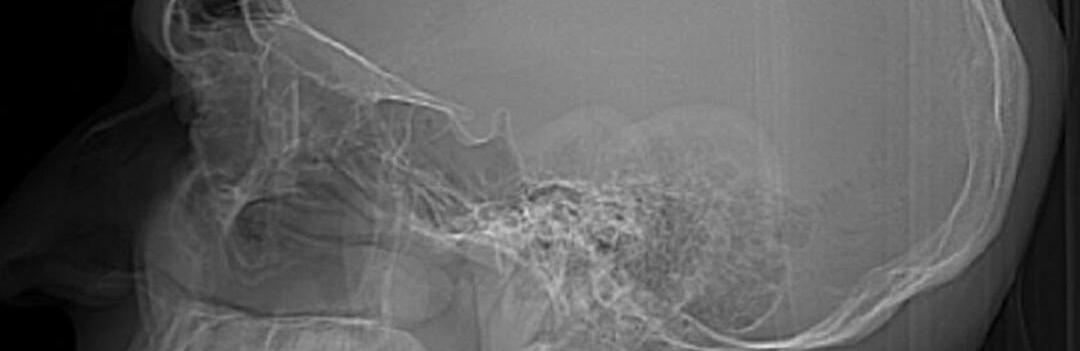

Просверлил череп дрелью: в Алматы россиянин вживил себе в мозг чип

Житель Новосибирска, с недавних пор находящийся в Алматы, самостоятельно в домашних условиях вживил себе трепанацию черепа ru.sputniknews.kz »